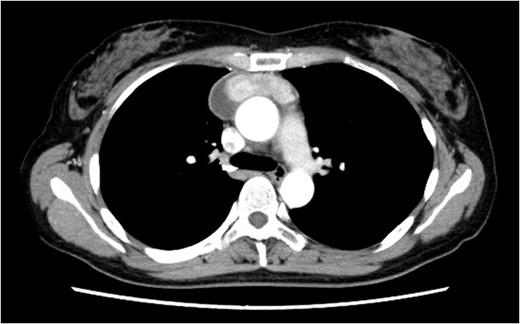

Four days after fasting, we resumed the normal diet and pleural fluid changed to slightly milky again. To specifically identify the location of and reduce the chyle leakage, lipiodol lymphography was attempted in the supine position through the right inguinal lymph nodes. The lipiodol lymphography detected the suspicious location of the chyle leakage (Fig. 4). After this procedure, the amount of pleural effusion was further reduced. Chemical pleurodesis with OK-432 was also performed just to be sure. The chest tube was removed the next day. She was discharged 10 days after re-admission. Chylothorax has not recurred 3 months post-operatively.

The lipiodol lymphography detected the suspicious location of the chyle leakage (arrow).